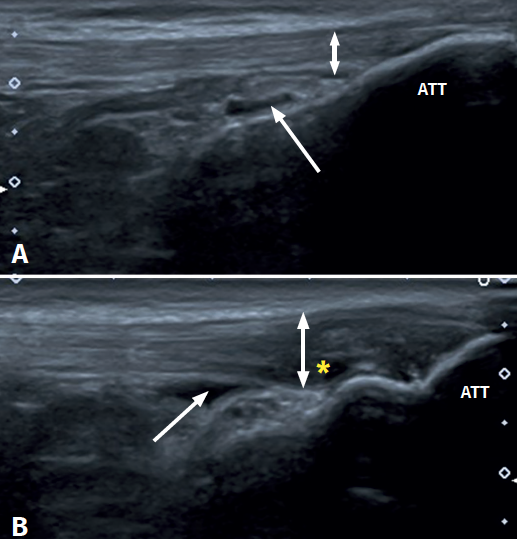

Tendinopatía rotuliana distal con bursitis infrarrotuliana

En la imagen A puedes ver la inserción distal de un tendón rotuliano sano. La flecha señala una bursitis leve y la doble flecha muestra el grosor normal del tendón.

En la imagen B, el tendón aparece engrosado (doble flecha) y ha perdido su patrón fibrilar homogéneo, viéndose más oscuro de lo normal. La flecha señala la bursa infrarrotuliana profunda con líquido en su interior, y el asterisco marca la zona donde las fibras de colágeno están desorganizadas.